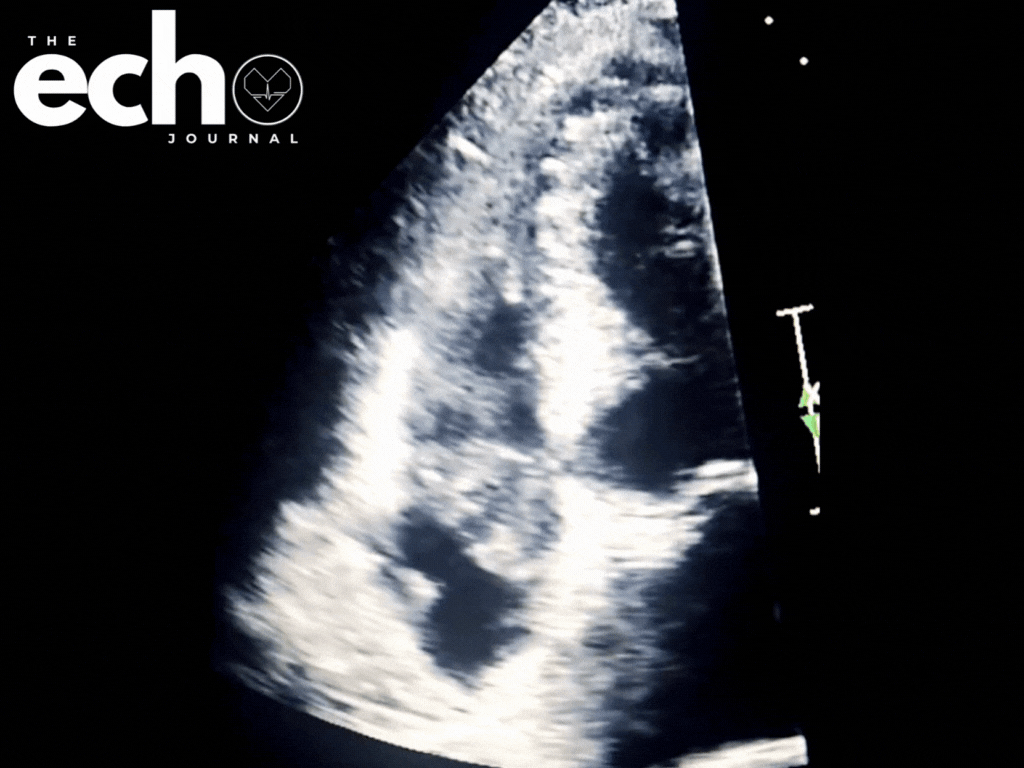

A large, mobile mass swings through the tricuspid valve with every heartbeat, leaving no doubt that this is real pathology.

When a finding is this obvious, it is tempting to stop at recognition. But vegetations are more than moving masses on a screen. Their location, mobility, attachment, and interaction with the valve all carry diagnostic and prognostic weight, and nowhere is that more apparent than on the tricuspid valve. This case uses a striking example, captured with TTE and TEE imaging, to break down what vegetations really look like on echocardiography and why the details matter.